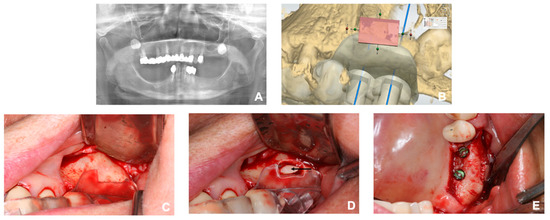

2.4. Surgical Procedure